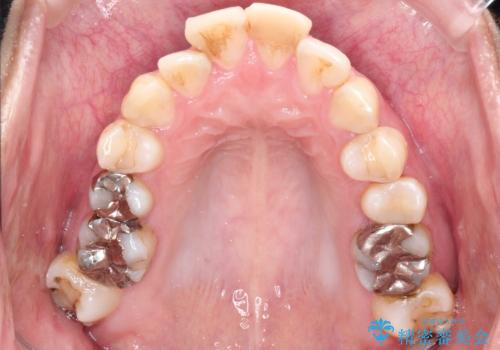

- 口元が出ていることを気にされて来院されました。精密な検査の結果、歯列全体のスペースが不足していることが判明。患者様のご希望である「口元を下げたい」というご要望を叶えるため、上下左右の小臼歯を抜歯し、そのスペースを利用して前歯を奥へ移動させる治療計画を立案しました。また、仕事上、目立つ矯正装置を避けたいというご希望から、上顎に裏側矯正、下顎に表側矯正を組み合わせたハーフリンガル矯正を提案しました。

今回の矯正治療では、口元を大きく下げるため、上下左右の小臼歯を抜歯しました。装置には、上顎は歯の裏側に装着する裏側矯正(舌側矯正)を、下顎は透明で目立ちにくい審美ブラケットを使用するハーフリンガル矯正を選択。これにより、治療中も他人の目を気にすることなく、ストレスなく過ごしていただけました。抜歯によってできたスペースを有効活用し、歯列全体を後方へ移動させることで、口元の突出感を解消。治療の結果、口元がすっきりと整い、自信のある美しい横顔を獲得していただけました。